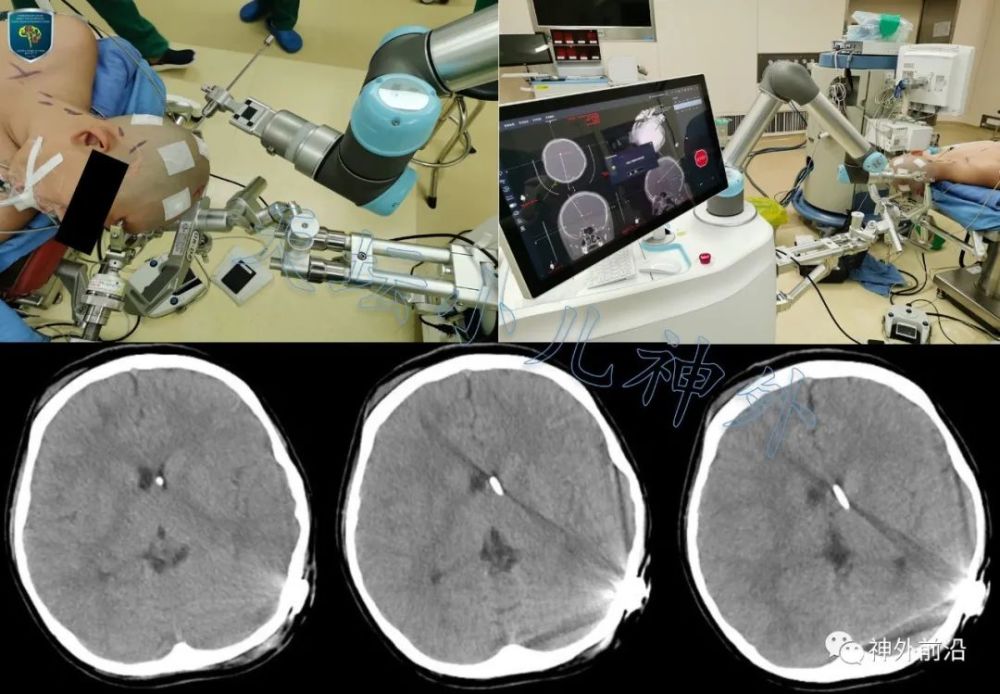

在术式选择上 , 我们认为首选侧脑室-腹腔分流术解除高颅压危象 。 由于分流管依赖综合征的患儿脑室极度缩小,呈裂隙状态 , 侧脑室体部的最宽径往往不超过3mm31 , 放置分流管非常困难 。 如果不能准确定位 , 反复多次脑室穿刺 , 很容易导致脑出血及脑损伤;即使侥幸放入脑室内 , 也不能保证分流管位置良好 。 分流管位置不佳会大大增加分流管堵塞的风险 , 导致手术失败32 。 因此 , 我们采用机器人辅助术中导航(图4上) , 穿刺误差控制在2mm以内 , 安全有效(图4下) 。 基于导航辅助的分流手术成功率远高于手工盲穿(90% vs 68%)33 , 值得推广 。

图4. 手术机器人导航辅助分流管脑室端精准置入左侧脑室额角 。